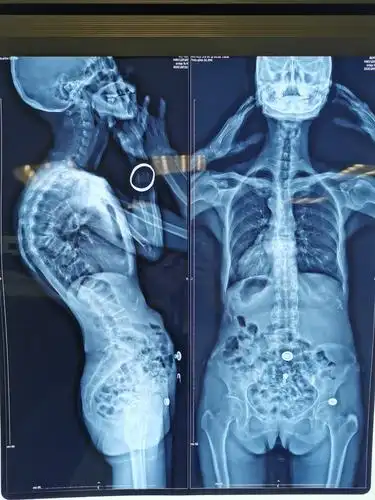

黎燕清,女,56岁,胸椎后凸畸形,t8,9椎体骨折,as并al,op,清远职工医保

胸腰段后凸cobb角42度,侧凸约20度.